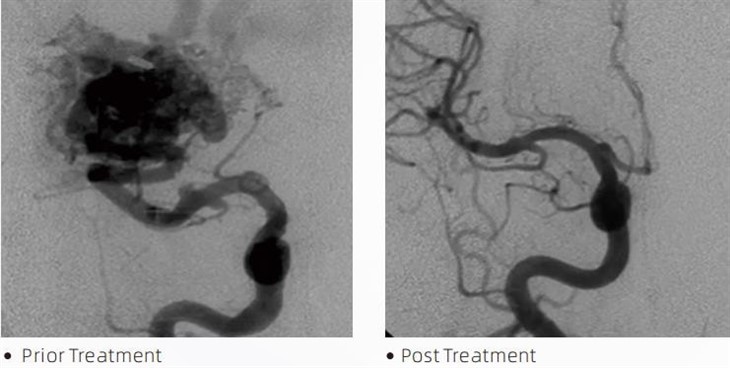

ЛаваТМемболични лепак је медицински уређај који користе интервентни неурорадиолози током минимално инвазивних процедура за лечење стања као што су церебралне анеуризме, артериовенске малформације и тумори. Лава емболички лепак нуди вишеструке предности како медицинским радницима тако и пацијентима у смислу безбедности, лакоће употребе и ефикасности. Лава је у стању да затвори крвне судове брзо и ефикасно. Процес укључује убризгавање лепка директно у циљани суд, где се полимеризује и стврдне у масу сличну ливењу која испуњава анеуризму или малформацију. Затим ефикасно прекида доток крви до лезије, спречавајући њено пуцање и смањујући ризик од трајног оштећења или можданог удара. Лава укључује Лава-12, Лава-18 и Лава-34. Свака формулација је дизајнирана да задовољи специфичне клиничке потребе. Лава-18 је стандардна формулација за општу употребу. Лава-34 је лепак високог вискозитета за посуде великог протока. Док Лава-12 има нижи вискозитет и проточнија је, што омогућава дисталне микровезице. Са овим опцијама, интервентни неурорадиолози могу изабрати одговарајуће Лава формулације како би осигурали оптималне резултате. Једна од најистакнутијих карактеристика Лаве је њена нелепљива својства. Ова супстанца је специјално формулисана да остане стабилна док не дође до циљаног подручја. Ова карактеристика значи да се Лава емболички лепак може прецизно поставити унутар артерије и остати тамо без лепљења или везивања за околно ткиво.